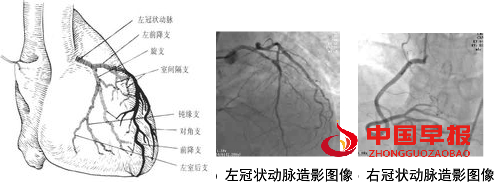

冠状动脉造影是诊断冠状动脉粥样硬化性心脏病(冠心病)的一种常用而且有效的方法,被称为诊断冠心病的“金标准”。心电图显示缺血,有心闷、气短、胸痛等心肌梗死先兆时,要做个冠状动脉造影检查,以便及时发现及时治疗,避免心肌梗死发生。

冠状动脉造影检查需要住院一天,桡动脉穿刺径路在拔除鞘管后对穿刺点局部压迫4-6小时后可以拆除加压绷带。股动脉入路进行冠状动脉造影后,18-24小时后可以拆除绷带开始轻度活动。如果使用封堵器,患者可以在平卧制动后6小时开始床上活动。